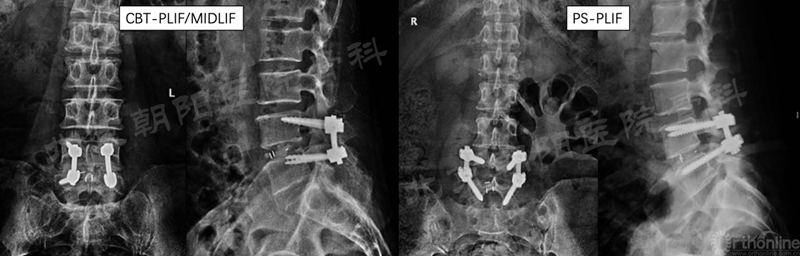

一、CBT-PLIF vs. PS-PLIF循证对比

本团队(首都医科大学附属北京朝阳医院)通过前瞻性队列研究对比了CBT技术和PS技术在腰椎融合中的应用,相关研究发表在Clinical Interventions in Aging和BMC Musculoskeletal Disorders杂志,主要研究结论如下: